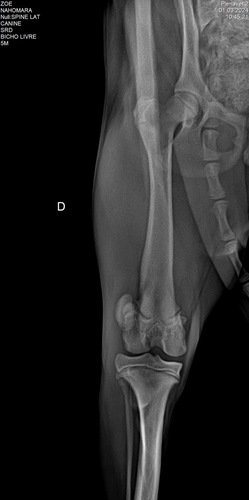

Nossa família adotou ela fazem 3 meses e ela está com a patela machucada ! Sendo assim precisa de uma cirurgia !!! 3.700,00 valor inicial sem os remédios! Já gastamos mais de mil reais até agora em remédios e consultas exames!!!